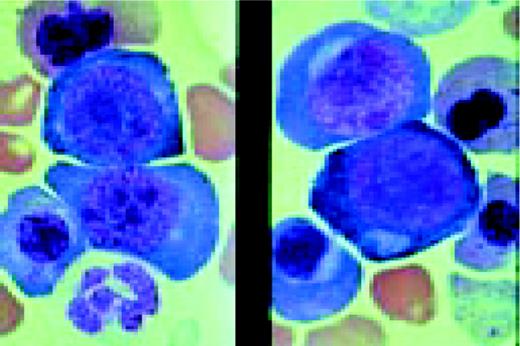

Slide M16

Acute nonlymphoblastic leukemia, FAB classification M5a (L) and M5b (R). The M5a blasts have a moderate amount of cytoplasm and somewhat coarse nuclei. The nucleoli are not unusually prominent. The blasts were positive with the nonspecific esterase stain, and the patient had an associated t(9;11) chromosome abnormality.

The predominant M5b cell is a promonocyte. This cell is characterized by abundant cytoplasm with numerous scattered azurophilic granules and a nucleus with finely dispersed nuclear chromatin. The nuclei are marked by extensive lobulation and creasing. Some of the nuclei have a cerebriform appearance.FIG69